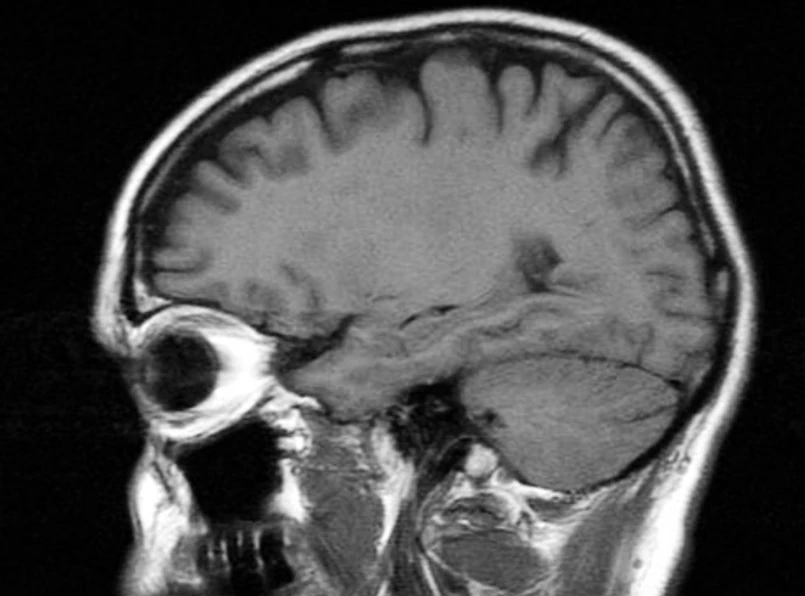

Po raz pierwszy poznaliśmy czyjeś myśli, patrząc wyłącznie na to, co robi jego mózg - twierdzą brytyjscy naukowcy. Patrząc na aktywność poszczególnych rejonów mózgu, badacze potrafili określić, o jakim miejscu myśli dana osoba.

Ludzki mózg uchylił swą kolejną tajemnicę. Tym razem - neurologom z brytyjskiego University College w Londynie. Obiektem ich badań był hipokamp - struktura mózgu znana z tego, że odpowiada za proces zapamiętywania. Brytyjczykom udało się jednak dowiedzieć, w jaki sposób obrazy są w nim przechowywane i odtwarzane.

W ramach naukowcy poprosili ochotników o zapoznanie się i zapamiętanie kilku W czasie, gdy badani zwiedzali wygenerowane przez komputer miejsca, badacze rejestrowali aktywność przy pomocy . Urządzenie to jest powszechnie wykorzystywane w diagnostyce medycznej i umożliwia sprawdzenie, które rejonu mózgu są w danej chwili aktywne, wiążąc je tym samym z określonymi czynnościami lub procesami. "Chcieliśmy się przekonać, czy może bycie w określonych miejscach skutkowało określonym wzorem aktywności hipokampa" - wyjaśnia prof. Eleanor Maguire, autorka badań.